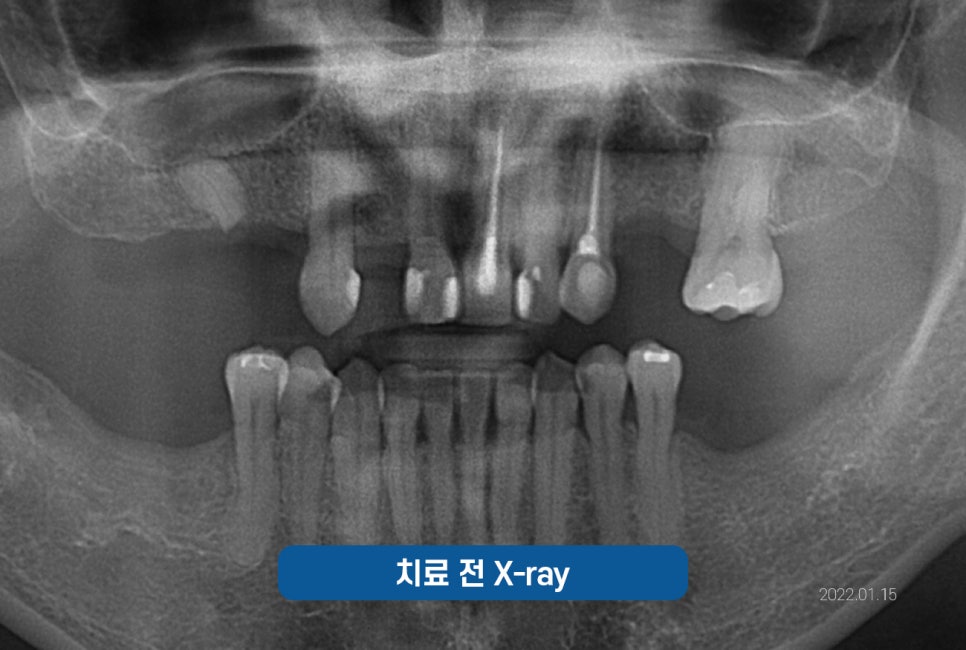

진료 받으신 분의 케이스를

한번 살펴보겠습니다.

*이해를 돕기 위해 동의 후 사용한 증례로

진료의 결과는 개인에 따라 달라질 수 있으니

주치의와 충분히 의논한 후 결정하시기 바랍니다.

잠원역치과 임플란트 케이스

상의를 한 후, CT촬영에 들어갔고

한번 더 체크를 한 후

수술 준비에 들어갔습니다.

심한 풍치로 흔들림이 심하고

예후가 안 좋은데

평소 불편한 점이 없었냐고 여쭤보니

잇몸이 좋지 않아 잦은 출혈이 보였고

흔들림이 심해 앞니로 베어먹기에 힘들어

고민이 많으셨다고 하셨습니다.

그래서 치아를 최대한 살리는 방향으로

고민을 해 보았으나,

이미 수명을 다한 치아로

안타깝지만 발치를 하기로 결정내렸습니다.